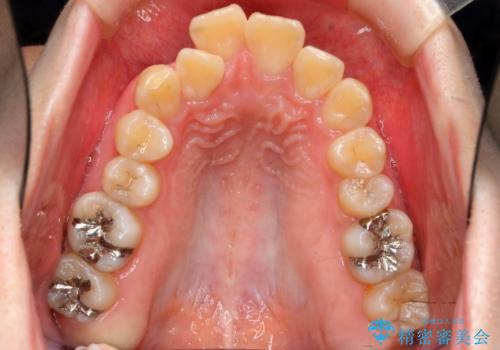

- 前歯のがたつき、前突を主訴に来院。

通常前から4番目の歯を抜歯するのですが、左上5番の形が矮小であったため、そちらを抜歯しました。(患者様の希望にそっています。)

前から5番目の歯を抜くと、長くて1年ほど矯正期間が延長しますが、形に異常がない左上4番を抜かずに保存しています。

治療は長くかかりましたが、正常な形の歯をのこすことができました。